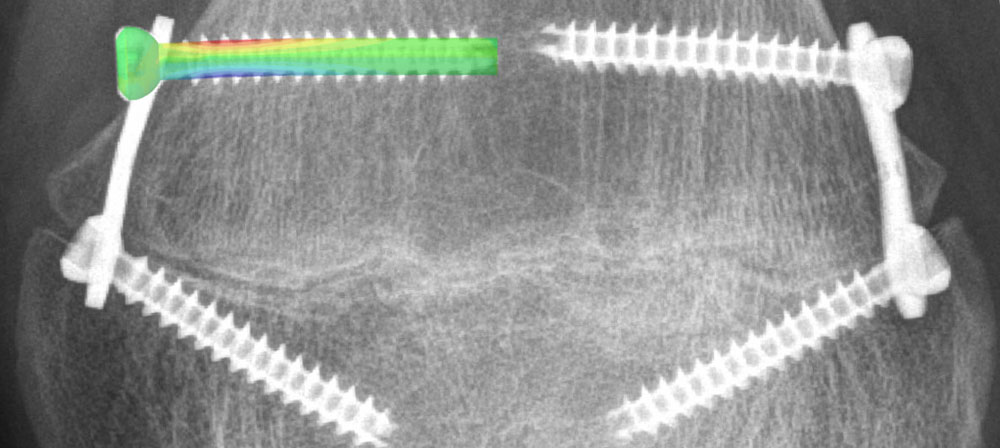

The Biomedical Development Program provides solutions with high translational potential to advance patient care by addressing contemporary clinical challenges in traumatology and orthopaedics mainly related to bone fracture fixation, joint reconstruction, and bone healing. In this regard, cutting-edge research is combined with development of innovative technologies and implants for orthopaedic applications and educational purposes. The multidisciplinary R&D team, consisting of physicists, engineers, orthopaedic trauma surgeons and technicians, utilizes extensive know-how, expertise and experience in the fields of biomechanical testing, computational analyses, and medical device and technology development, workings in close collaboration with clinical, scientific, and industrial partners, as well as with the AO Clinical Divisions and AO Innovation Translation Center.

- To perform experimental and computational studies enhancing bone fracture fixation